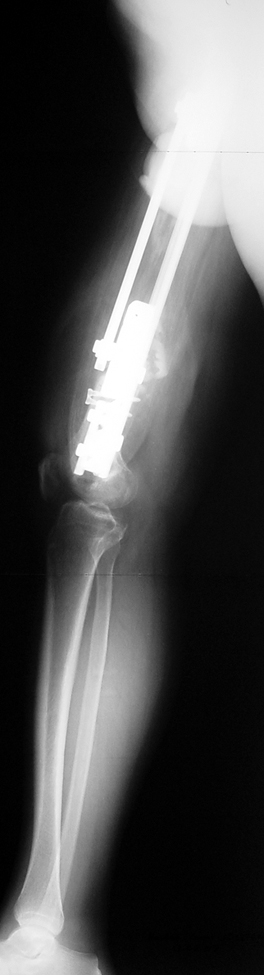

The duration of external fixation (external fixation index) depends on the amount of distraction required, and the extremity is prone to complications during this period. After the distraction phase is completed, the external fixator remains in place during the consolidation phase, which lasts twice as long as the distraction phase; but this period is hardly tolerated. If the external fixator is removed before sufficient consolidation is achieved, fractures, deformity and shortness will be the result. In our department, ‘lenghthening over nail’ method is used in order to decrease the external fixation index and increase patient comfort and activity level. In this method, the intramedullary nail is statically locked after the completion of the distraction phase, and external fixator is removed. The extremity is stabilized by the intramedullary nail during consolidation phase. In this way, complications due to long external fixation index or early removal of the external fixator are avoided.